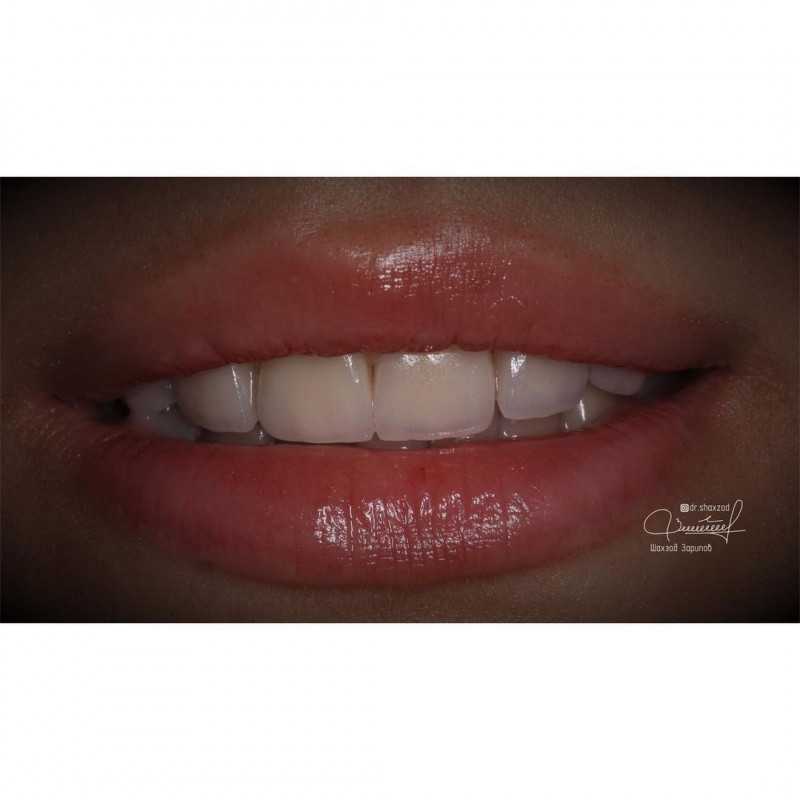

4 работы в портфолио

Зарипов Шахзод Журакулович принимает в круглосуточной стоматологии СПЕЦИАЛИСТ в Москве. Стаж 7 лет. Специализируется на терапевтии и ортопедии, по которым клиника оказывает 21 услугу. Имеет 4 работы до/после в портфолио. Для уточнения дополнительной информации о специалисте или записи на прием можно позвонить по телефону